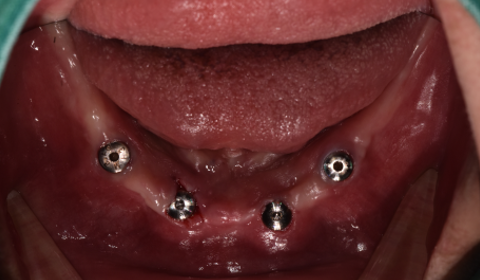

임플란트 식립

전체 틀니를 다시 제작하는 방법도 있지만, 최소한의 임플란트로 틀니를 잡아주는 치료를 결정하였습니다. 고령인 점 고려하여 무리가 가지 않게 무절개/최소절개로 4개의 임플란트를 식립하고 임플란트 똑딱이 장치를 이용하여 임플란트와 기존 쓰시던 틀니를 연결하였습니다.